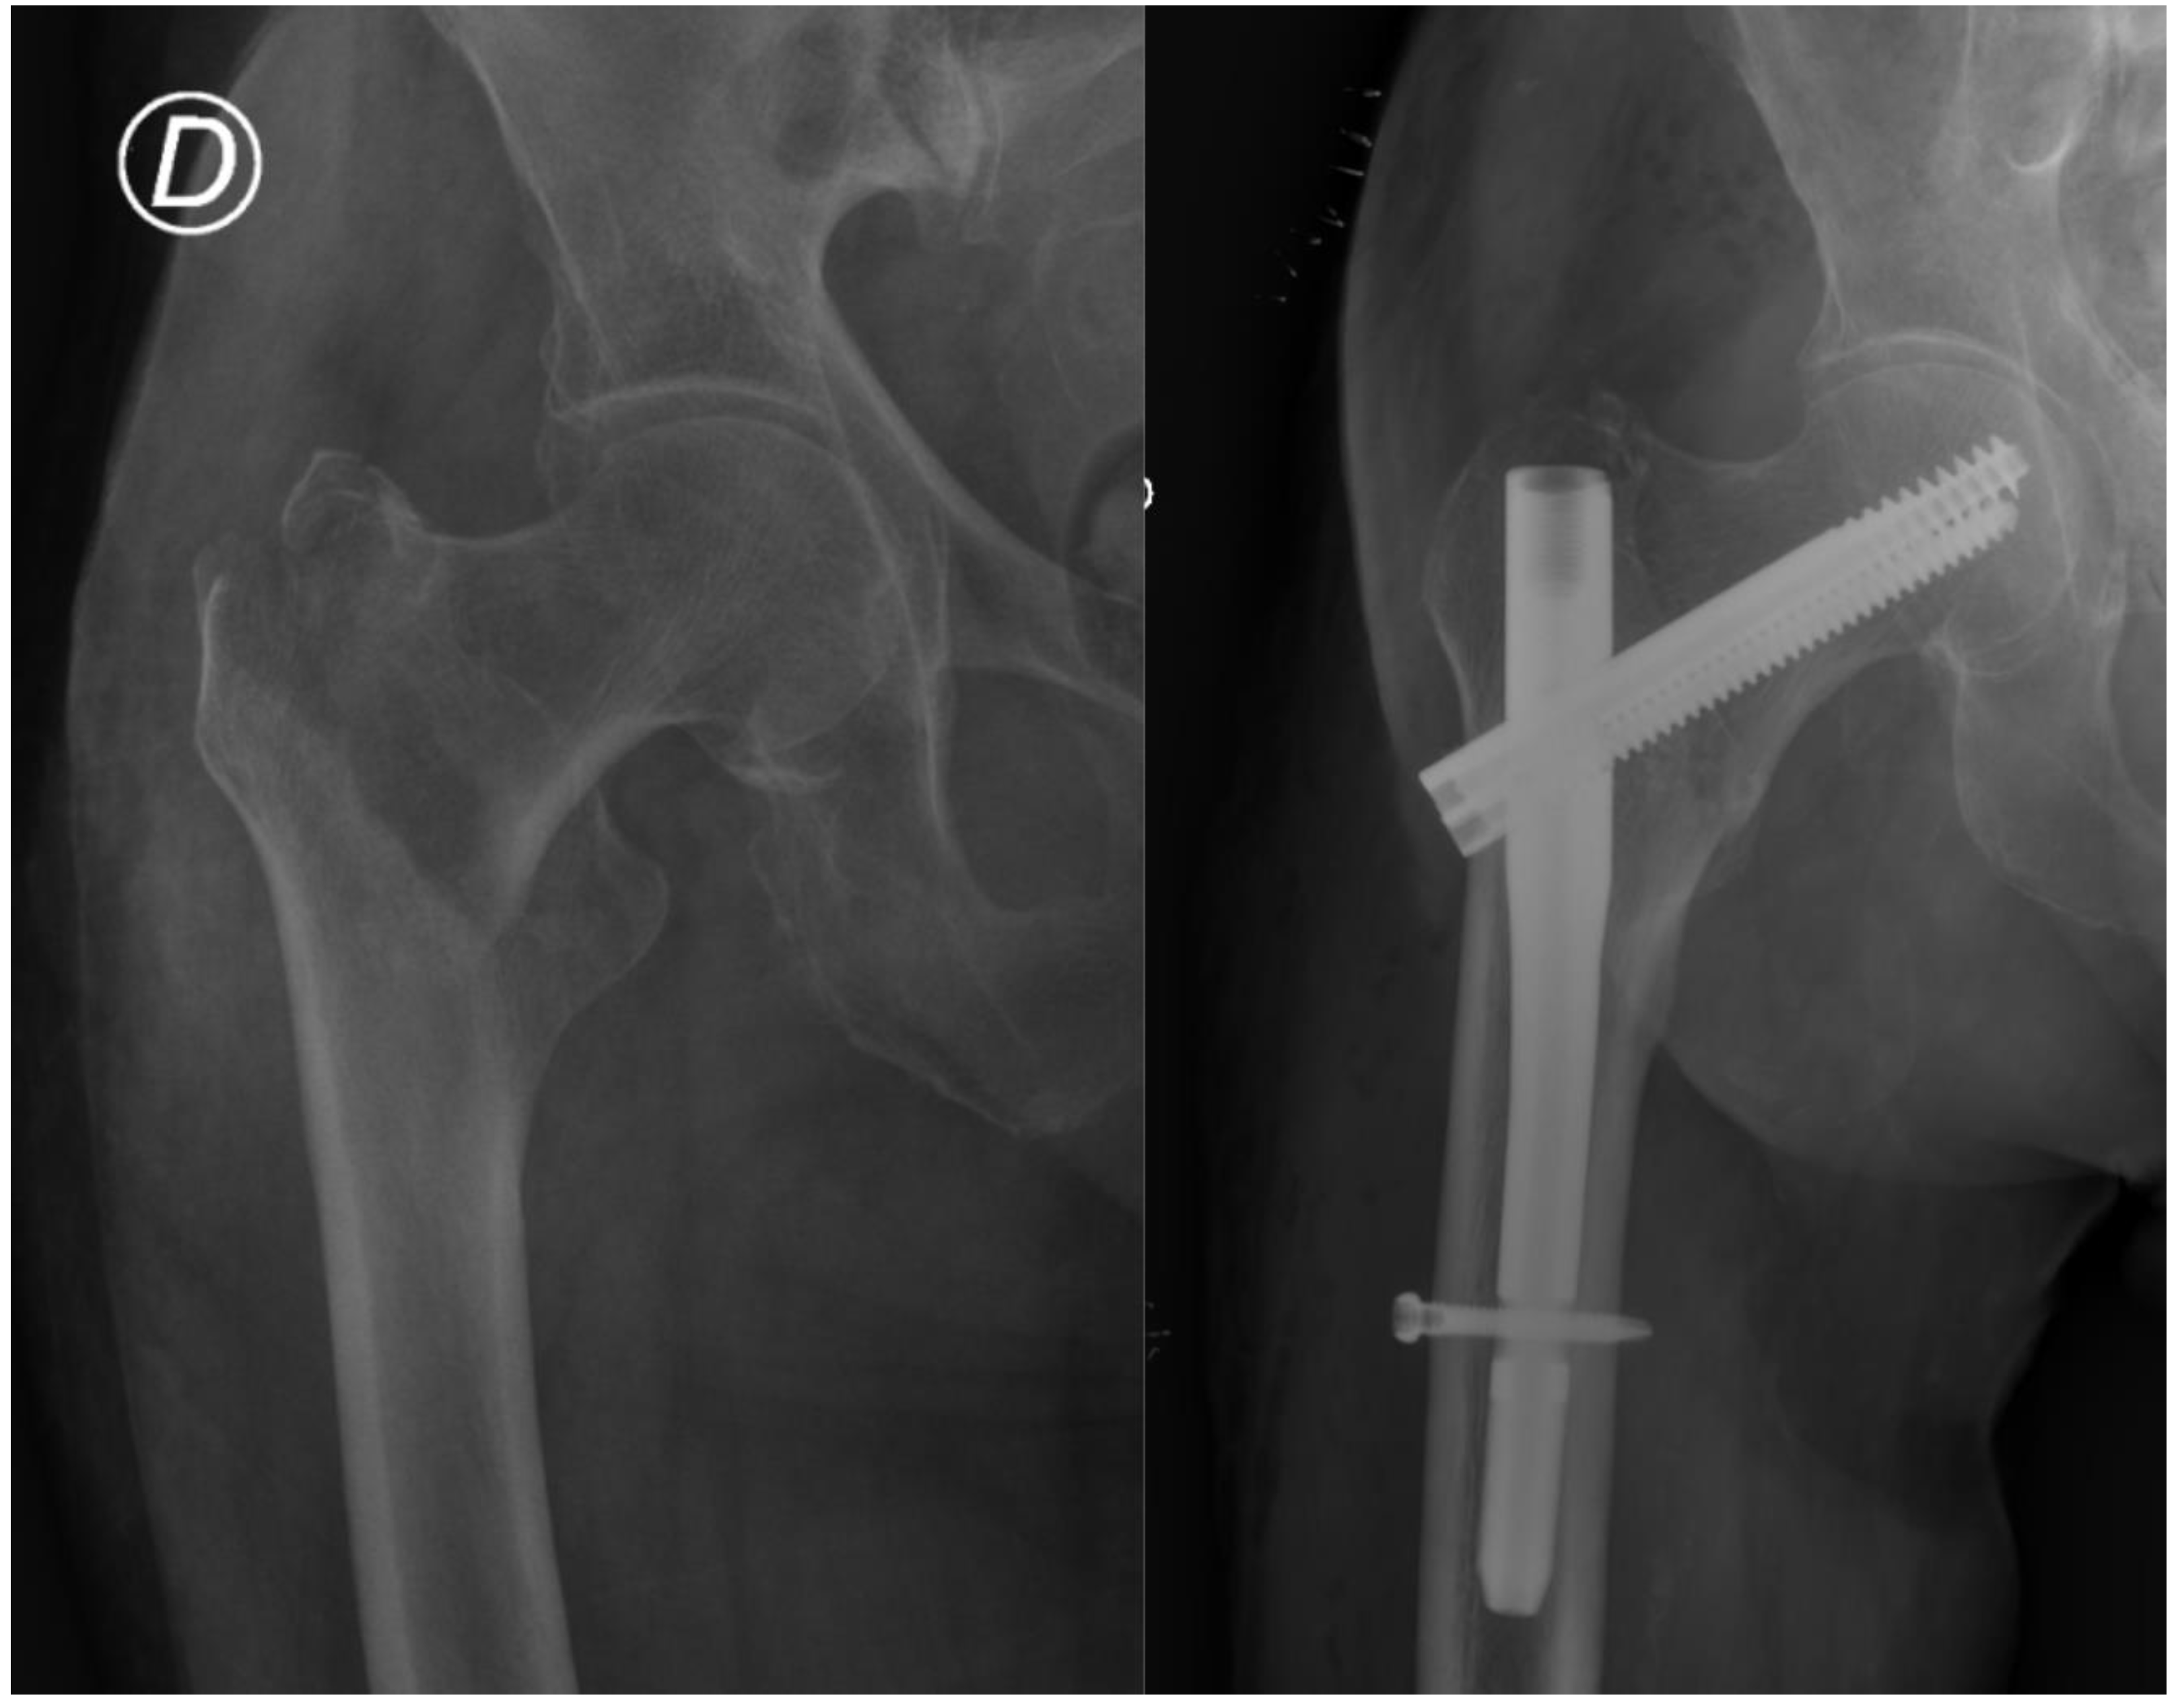

Treatment of Trochanteric Hip Fractures with Cephalomedullary Nails: Single Head Screw vs. Dual Integrated Compression Screw Systems

| Reoperations in the follow-up period after surgery, n (%) | 17 & (4.4%) | 6 (2.3%) | 11 & (8.8%) | 0.008 |

| Reoperation required, rates at 1.5 Years Following Surgery *, % | 5.8% | 1.9% | 13.3% | 0.009 |

| Cut-out | 8 (2.1%) | 2 (0.8%) | 6 (4.8%) | 0.016 |

| Peri-implant fracture | 6 (1.6%) | 2 (0.8%) | 4 (3.2%) | 0.089 |